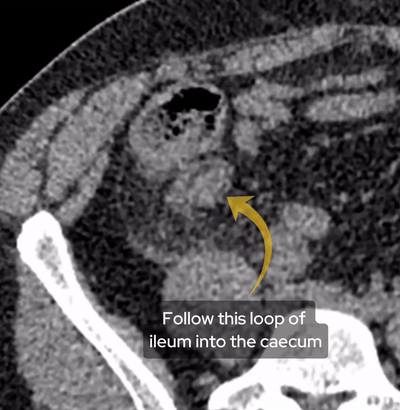

Due to pain the patient could only tolerate a few STIR sequences so we don’t have a complete scan but have a look at this axial STIR sequence below. We have high STIR signal within the right psoas with locules suggesting abscess formation.

Have a look at this axial STIR image from the MRI scan. Here we have high SITR signal within the right psoas with locules suggesting abscess formation.

If we look at a lateral STIR sequence of the lumbar spine, we can see high signal in the lateral aspect of the L3-4 disc which is continuous with the abscess formation within the right psoas. This highly suggests a spondylodiscitis as the primary pathology leading to secondary psoas abscess.

When we scroll through this sagittal STIR sequence of the lumbar spine we will see high signal within the L3-4 disc adjacent to the right psoas abnormality.